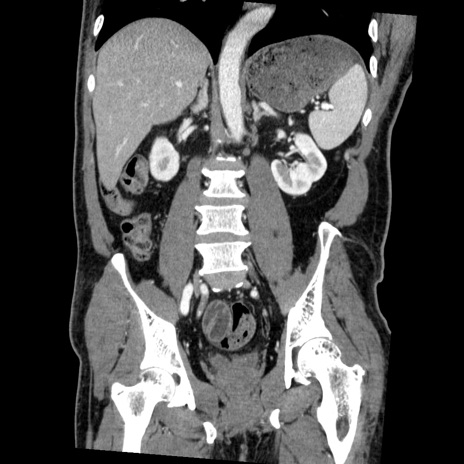

症例22(冠状断像)

【症例】50歳代男性

【主訴】腹痛

【現病歴】AVMからの被殻出血のため回復期リハ病棟入院中。 本日午後3時頃急に下腹部痛が出現した。

【既往歴】AVM、被殻出血、虫垂炎、高血圧

【身体所見】意識晴明、左半身不全麻痺、会話の理解は良好、36.5°C、腹部:膨隆、全体に板状硬、下腹部正中に圧痛点あり、反跳痛-、筋性防御不明、右下腹部にope scar

【データ】WBC 9400、CRP 0.06